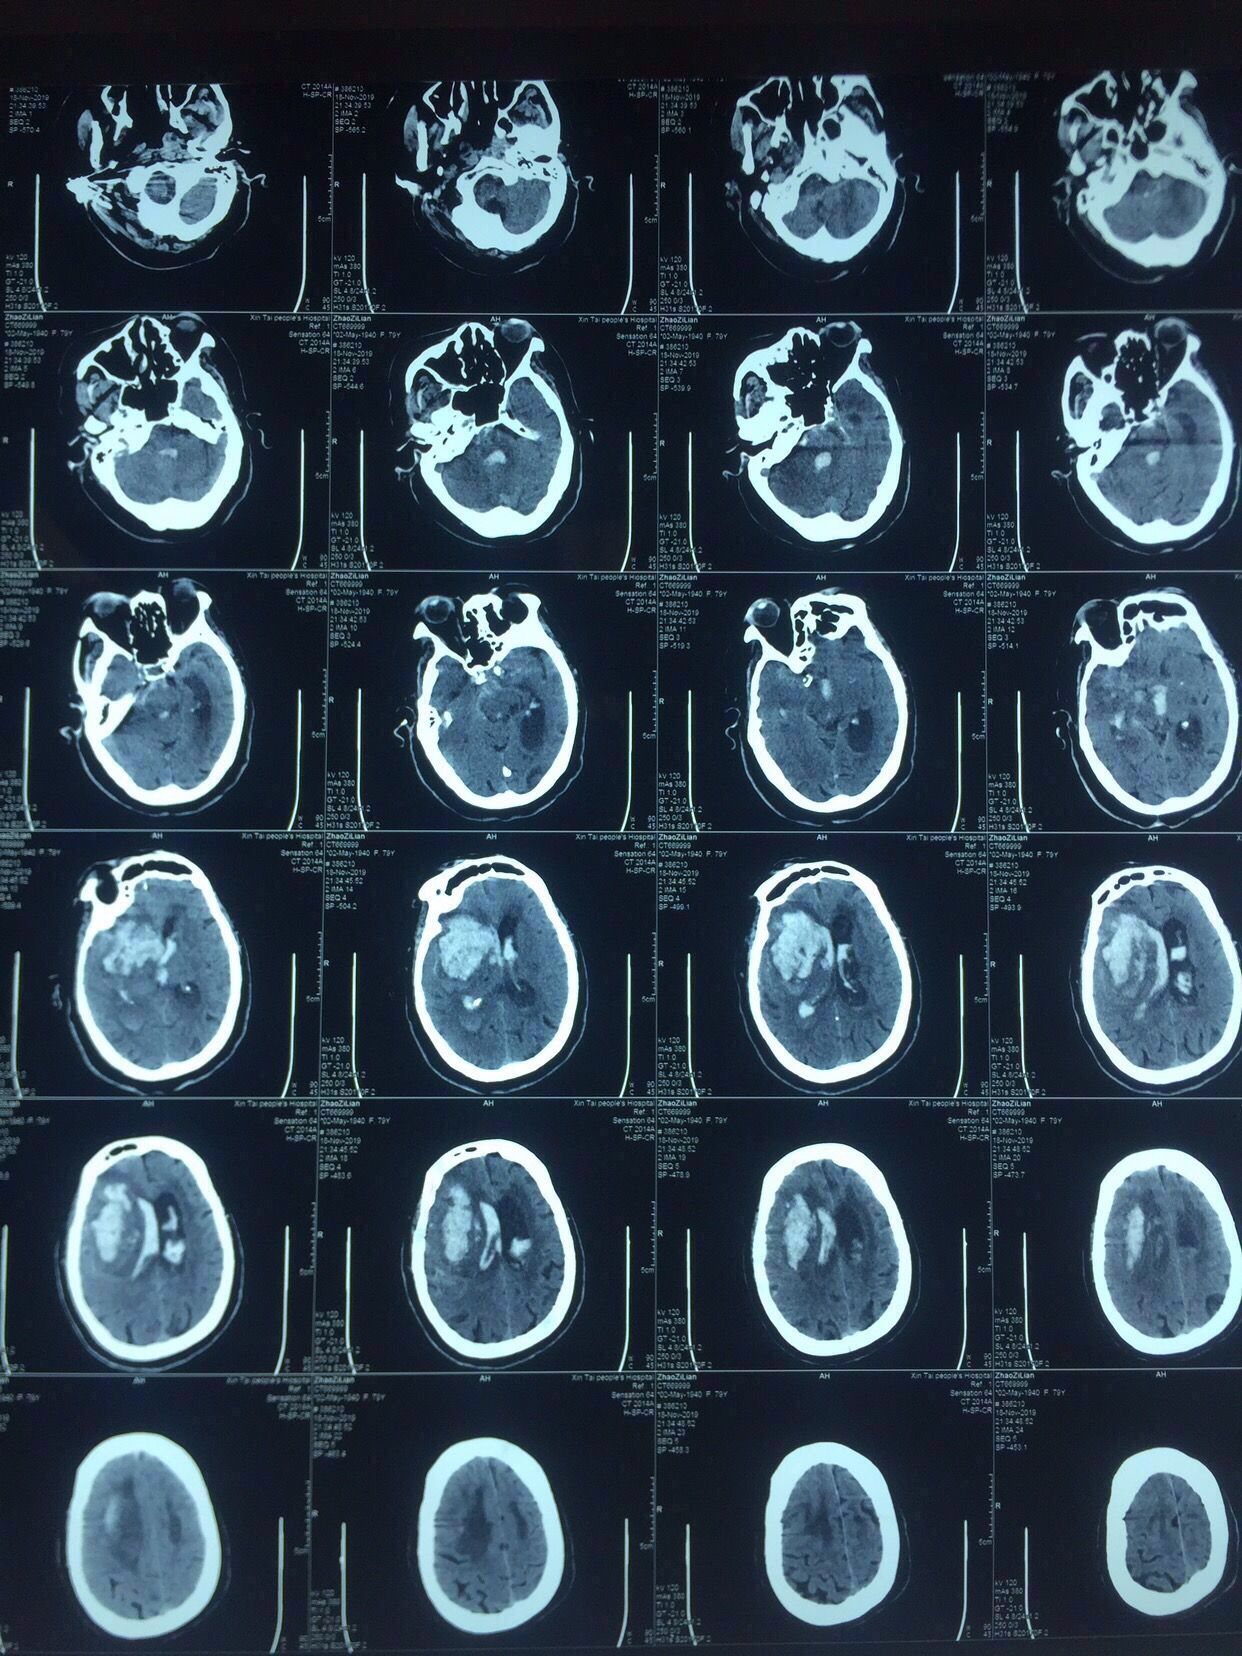

次日复查如上图:

出血未再增大。

中线旁开2.5㎝可以让穿刺管几乎游走在所有的血肿层面内↓↓↓↓↓↓4张照片

前后对比图如下↓↓↓